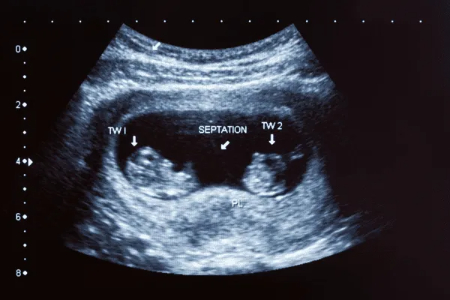

- سیستم قلبی و عروقی: قلب جنین به طور کامل به چهار حفره اصلی نزدیک میشود و ضربان قلب قویتر و منظمتر است. این ضربان قلب در سونوگرافی قابل مشاهده است.

در هفته هشتم، جنین حدود ۱.۶ تا ۲.۳ سانتیمتر طول دارد و وزن آن تقریباً ۱ تا ۲ گرم است. با وجود کوچک بودن، اندامها و سیستمهای حیاتی جنین در حال شکلگیری هستند و ضربان قلب آن قابل مشاهده است.